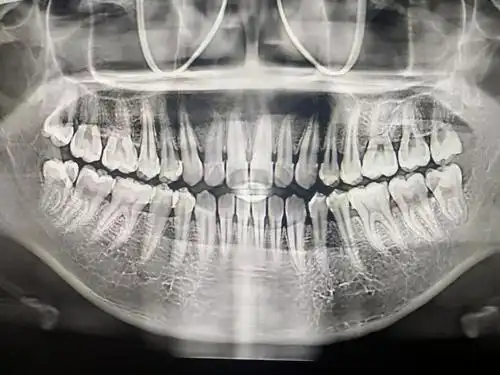

拍到,它的优点是可以展现出整个口腔里的牙齿及口腔周边解剖结构颌骨

刚刚拍的牙片

去年拍的牙片

正畸前的侧面正畸前的牙齿由于我的牙齿状态比较差,上齿右5早期补过牙